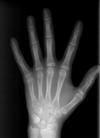

Eine besondere Aufnahme ist das Röntgen der Handknochen zur Bestimmung des vorhandenen Wachstums des Patienten, da bestimmte kieferorthopädische Maßnahmen das Wachstum für den Erfolg erfordern (z.B. Korrektur der Unterkieferlage). Daneben ist es möglich, die spätere Körpergröße des Kindes zu berechnen.